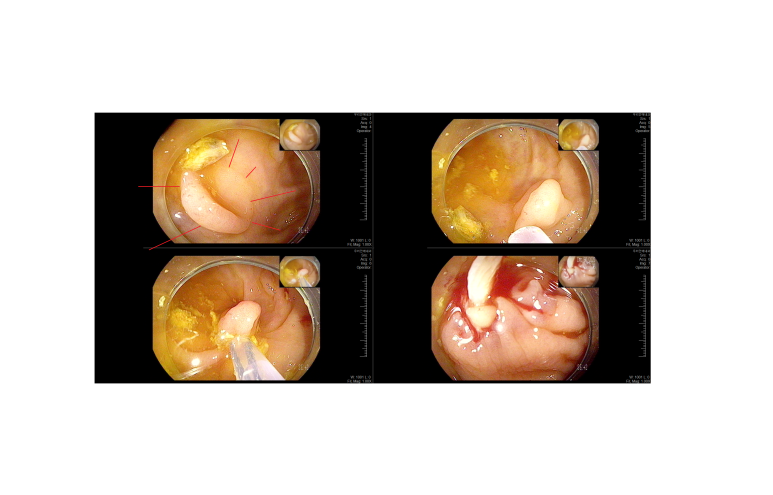

진입시 작은 용종은 선종

이후 9 mm 크기의 육안적 과증식용종/거치상 용종은 용종절제술로 제거하였으나 조직검사에는 과증식을 주었다.